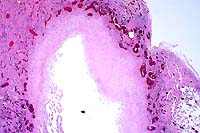

- Case III - 537-98 (AFIP 2656747)

-

- Signalment: Seven-week-old broiler breeder pullets

(chicken).

- History: There was increased mortality of 3-4 days

duration. Affected birds were lethargic, inappetent, and had

ruffled feathers and mild to moderate loss of pectoral muscle

mass. A few birds had red-brown feces.

- Gross Pathology: Moderate to marked loss of pectoral

muscle mass was present. Gross lesions varied with chronicity,

ranging from marked hyperemia and mild ulceration of the cecal

mucosa to extensive ulceration of the cecal mucosa with large

fibrinonecrotic casts within the lumens. In virtually all birds,

there was moderate to marked thickening of the cecal walls. The

livers of several birds contained variably-sized, often coalescing,

foci of necrosis. In a few of the birds, there was rupture of

the cecum with extensive fibrinous peritonitis and airsacculitis.

Small numbers of cecal worms (Heterakis gallinarum) were variably

present in the cecal lumen.

- Case 16-3. Liver. Liver parenchyma is multifocally

necrotic and partially replaced by myriad Histomonas trophozoites,

10-20u in diameter, which are fragmented, pale, amphophilic,

and surrounded by narrow rims of clear space.

- Case 16-3. Colon. The lamina propria is diffusely

expanded by macrophages, lymphocytes, heterophils, and fragmented,

pale, granular Histomonas amoeba. At points of mucosal erosion,

these inflammatory cells stream into the gut lumen.

AFIP Diagnoses:

- 1. Liver: Hepatitis, granulomatous, necrotizing, multifocal

to coalescing, moderate, with numerous protozoa, chicken, avian.

- 2. Cecum: Typhlitis, lymphoplasmacytic, histiocytic, and

heterophilic, diffuse, moderate, with protozoa and cecal core.